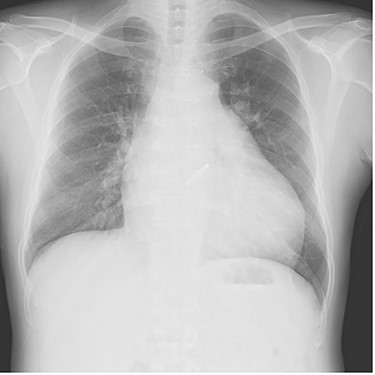

Chest radiography showed an enlarged heart with a cardiothoracic ratio of 73% and right pleural effusion (Fig. 1). Laboratory test results were as follows: blood urea nitrogen, 48.1 mg/dl; creatinine, 1.96 mg/dl; total bilirubin, 2.7 mg/dl and N-terminal prohormone of brain natriuretic peptide: 3043 pg/ml. Transthoracic echocardiography revealed ejection fraction of 49%, severe AR, mild to moderate mitral regurgitation, severe pulmonary regurgitation and mild to moderate tricuspid regurgitation. The pulmonary valve’s maximum pressure gradient had decreased from 31 mmHg 8 months previously to 5 mmHg. The diameter of the ascending aorta was 39.2 mm, sinotubular junction was 36.1 mm and Valsalva sinus was 47.4 mm. Cardiac catheterization showed no significant coronary artery stenosis.

Plain chest radiograph of the first outpatient visit after discharge from the hospital.